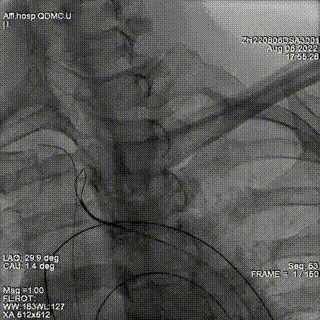

根据造影确定瓣周漏位置,在第一个封堵器旁探查,再次通过瓣周漏,置换鞘管后置入第2枚封堵器,仍选择6mmADOII。封堵器释放后位置良好。

超声提示2枚封堵器位置良好,瓣周反流明显减少,但仍有少-中量瓣周反流。遂在已植入封堵器旁再次探查,并通过瓣周漏。因交换鞘管困难,遂采用LOOP法建立轨道,引导输送鞘管通过瓣周漏。

释放第三枚封堵器,选用6mmADOII,释放后造影显示无明显瓣周反流。